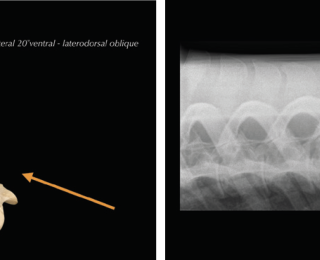

• Radiography allows the visualisation of the vertebral column, intervertebral articulations (IVAs/’facet joints’) and vertebral bodies to a varying degree, depending on location, equipment and patient size. Latero-lateral views as well as oblique projections can be obtained. Standard radiographs ideally include three to five overlapping latero-lateral radiographs using radiopaque markers, such as coins, for orientation. Collimated views of specific regions of interest can help to increase image quality by reducing scatter. Main limitations of the technique include attenuation and inability to visualise lumbar vertebral bodies. Care should be taken when interpreting or measuring interspinous spaces (ISS). Geometric distortion markedly affects the appearance of the spaces, depending on the shape and the distance of the dorsal spinous processes to the focal spot emitting X-ray beams (Djernæs et al 2017). Furthermore, the head position influences the distance between thoracic dorsal spinous processes and it is therefore advised to acquire back radiographs in a neutral position with the muzzle at shoulder level (Berner et al 2012). To further assess intervertebral articulations, oblique projections are obtained with the beam angled 20˚ from ventral to dorsal and centred 15-20cm ventral to dorsal midline (Butler et al. 2000; Girodroux et al. 2009). The X-ray plate should be aligned perpendicular to the beam and as close as possible to the horse. The highly-curved shape of the ribs is causing superimpositions with to the thoracic IVAs. In the lumbar spine there is superimposition of the transverse processes and abdominal structures.